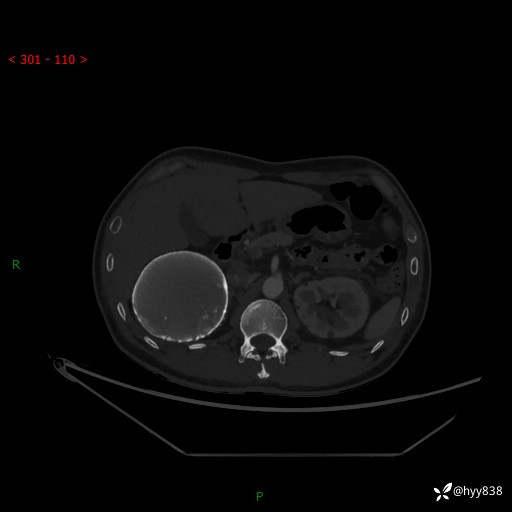

性别:男

年龄:50岁

简要病史:夜尿增多半月,发现肾功能异常1天,超声发现腹膜后占位

腹部CT平扫+增强

增强